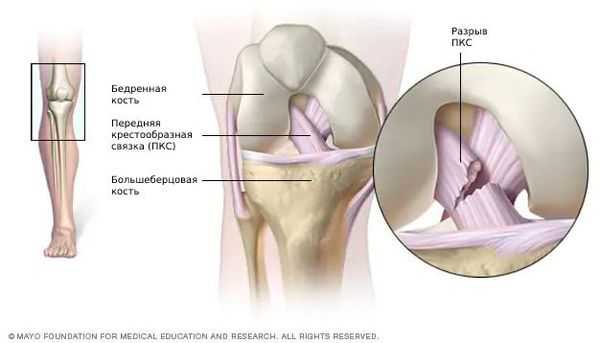

Разрыв передней крестообразной связки (anterior cruciate ligament injury) — это одна из самых тяжёлых травм коленного сустава. Повреждение сопровождается щелчком в колене и невозможностью продолжать физическую активность. Затем появляется отёк и становится трудно сгибать и разгибать ногу в суставе.

![Разрыв передней крестообразной связки [13]](/pimg3/priznaki-radialnogo-razriva-9977785.jpg)

Патогенез разрыва передней крестообразной связки

Передняя крестообразная связка состоит из спирально расположенных коллагеновых волокон, которые обеспечивают её прочность и растяжимость [7] [10] . Своим верхним концом ПКС прикрепляется к бедренной кости, а нижним — к большеберцовой. На середине хода ПКС пересекается с задней крестообразной связкой. И з-за характерного перекрёста данные связки и получили своё название [8] [9] .

![Передняя и задняя крестообразные связки [15]](/pimg3/priznaki-radialnogo-razriva-4A6CCBC.jpg)